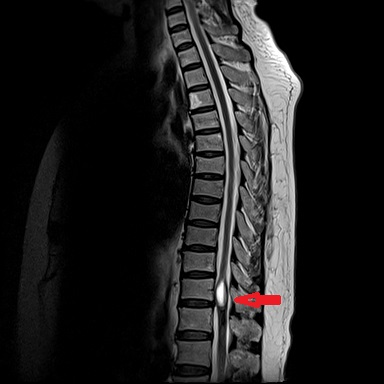

患者康婆婆(化名)今年已近70岁,因“右下肢麻木5+月加重伴疼痛3+月”前来医院治疗,行腰部核磁检查发现胸11椎体平面脊髓内囊性占位,考虑室管膜瘤的肿瘤性病变。患者下肢长期麻木伴疼痛,经神经外科医疗团队研究讨论,为患者行了微创的胸椎椎管骨质切开和脊髓内肿瘤病变的切除手术治疗,切除了患者的肿瘤后,患者下肢肌力和麻木感明显改善。

手术前检查

术后手术图片